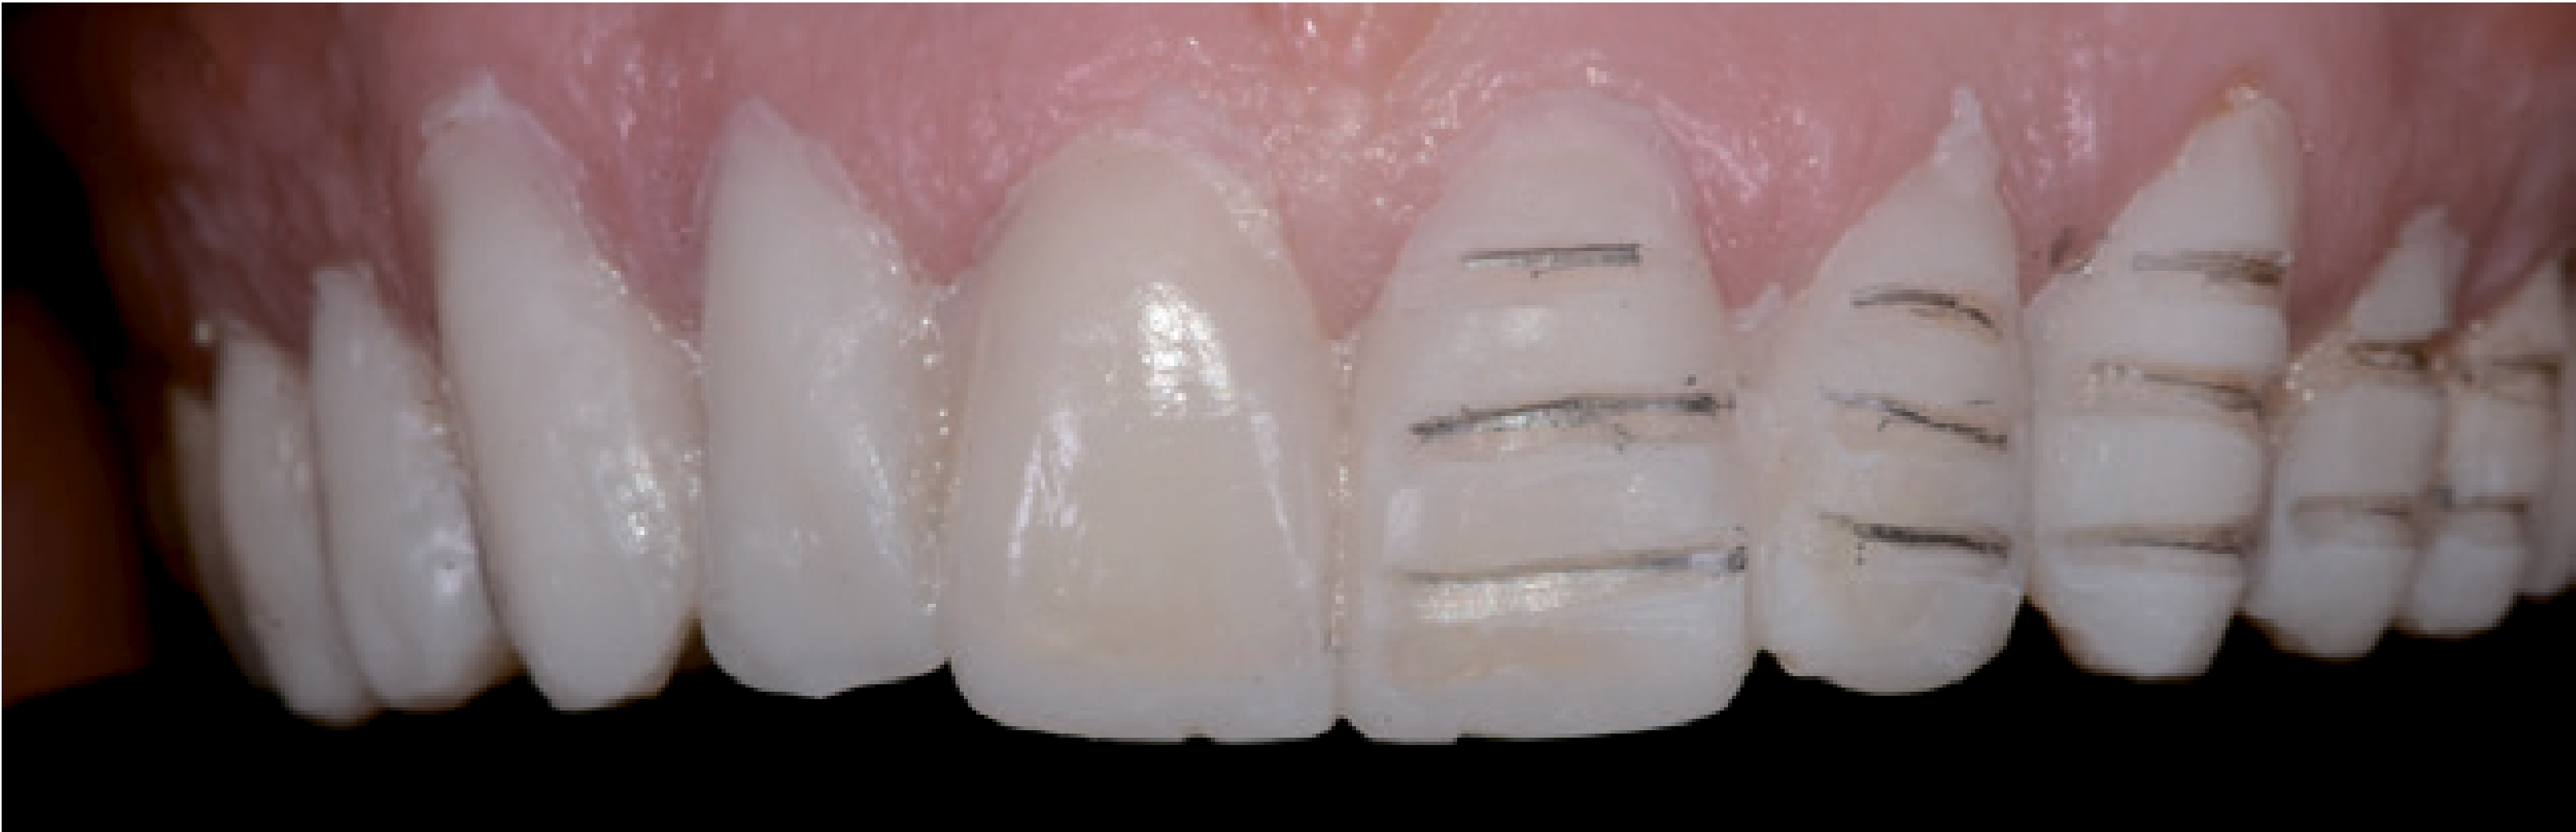

Щоб гарантувати мінімальну інвазивність і граничну точність під час препарування, ТЕМПО має залишатися в ротовій порожнині. У такий спосіб можна буде видалити стільки емалі, скільки потрібно. Щоб було зручніше направляти бор, початкове препарування проводили за допомогою ТЕМПО. За допомогою маркера глибини вирізали три горизонтальні насічки у пришийковій, центральній та різцевій зонах mock-up. На більш коротких премолярах зробили по дві горизонтальні насічки у такий самий спосіб (мал. 9).

Довжину різального краю зменшили за допомогою двох вертикальних вирізів не менше 1,5 мм, щоб надати технікові достатньо простору для роботи в цій важливій естетичної зоні (мал. 10).

Керуючись такими мітками-заглибленнями весь різцевий край рівномірно зменшили за допомогою препарування крайок стикового з'єднання або залишили недоторканим через збільшення завдяки ТЕМПО. Горизонтальні лінії препарування позначили олівцем. Залишки mock-up (ТЕМПО) видалили скалером. На поверхнях, частину яких потрібно було видалити під час препарування, залишилися сліди олівця (мал. 11).